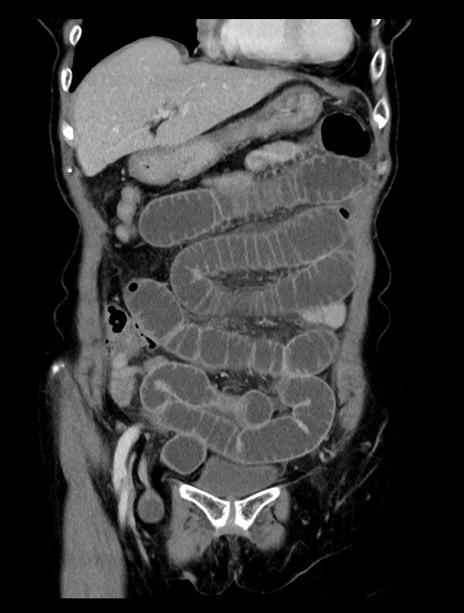

症例23(冠状断像)

【症例】70歳代女性

【主訴】下腹部痛・嘔吐

【現病歴】2日前より腹痛あり。昨日嘔吐あり。症状改善しないため来院。

【既往歴】胃GISTに対して胃部分切除後。

【身体所見】BT 37.1℃、BP 128/77mmHg、腹部:平坦・軟、下腹部に圧痛あり。

【データ】WBC 10200、CRP 0.31